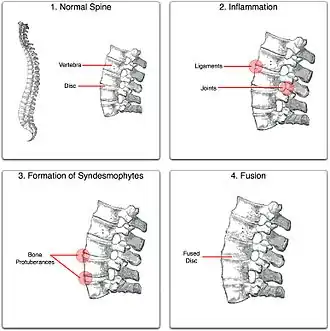

"Bamboo spine" develops when the outer fibers of the fibrous ring (anulus fibrosus disci intervertebralis) of the intervertebral discs ossify, which results in the formation of marginal syndesmophytes between adjoining vertebrae.

The earliest changes demonstrable by plain X-ray shows erosions and sclerosis in sacroiliac joints. Progression of the erosions leads to widening of the joint space and bony sclerosis. X-ray spine can reveal squaring of vertebrae with bony spur formation called syndesmophyte. This causes the bamboo spine appearance. A drawback of X-ray diagnosis is the signs and symptoms of AS have usually been established as long as 7–10 years prior to X-ray-evident changes occurring on a plain film X-ray, which means a delay of as long as 10 years before adequate therapies can be introduced.[25]

Prognosis is related to disease severity.[11] AS can range from mild to progressively debilitating and from medically controlled to refractory. Some cases may have times of active inflammation followed by times of remission resulting in minimal disability while others never have times of remission and have acute inflammation and pain, leading to significant disability.[11] As the disease progresses, it can cause the vertebrae and the lumbosacral joint to ossify, resulting in the fusion of the spine.[44] This places the spine in a vulnerable state because it becomes one bone, which causes it to lose its range of motion as well as putting it at risk for spinal fractures. This not only limits mobility but reduces the affected person's quality of life. Complete fusion of the spine can lead to a reduced range of motion and increased pain, as well as total joint destruction which could necessitate a joint replacement.[45]

Osteoporosis is common in ankylosing spondylitis, both from chronic systemic inflammation and decreased mobility resulting from AS. Over a long-term period, osteopenia or osteoporosis of the AP spine may occur, causing eventual compression fractures and a back "hump".[46] Hyperkyphosis from ankylosing spondylitis can also lead to impairment in mobility and balance, as well as impaired peripheral vision, which increases the risk of falls which can cause fracture of already-fragile vertebrae.[46] Typical signs of progressed AS are the visible formation of syndesmophytes on X-rays and abnormal bone outgrowths similar to osteophytes affecting the spine. In compression fractures of the vertebrae, paresthesia is a complication due to the inflammation of the tissue surrounding nerves.